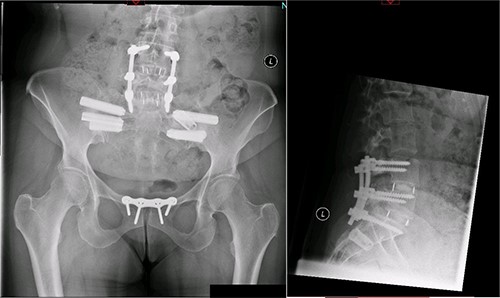

A magnetic resonance imaging (MRI) scan performed in October 2013 (Fig. 1) identified non-compressive, degenerated discs at L4/5 and L5/S1 vertebral levels. However, clinically as the patient was more tender over the left SI joint and the pubic symphysis (Fig. 2), a left sacroiliac joint fusion and symphysis pubis plating procedure was performed in August 2014 (Fig. 3). Following a short period of relief, the pain returned. Subsequently, the patient underwent a 360° fusion (front and back) of the L4/L5 and L5/S1 discs in August 2015 (Fig. 4), a year following the previous surgery. Once again, following a brief period of relief, the symptoms returned. The assumption then was that the initial fusion of the left sacroiliac joint had failed. Therefore, a revision fusion of the left sacroiliac joint and a primary fusion of the right sacroiliac joint was undertaken in August 2017 (Fig. 5).

Postoperative X-ray of the pelvis following the third fusion surgery: postoperative X-ray of the pelvis, performed in March 2021 following the third fusion surgery, showing refusion of the left sacroiliac joint and primary fusion of the right sacroiliac joint with the SI-bone implant.